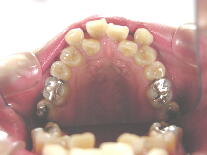

症例3 (30代 女性) 右下顎切歯先天性欠如

左右上顎第一小臼歯・右下顎第一小臼歯抜歯例

![]() ![]() ![]()

初診から4ヶ月後